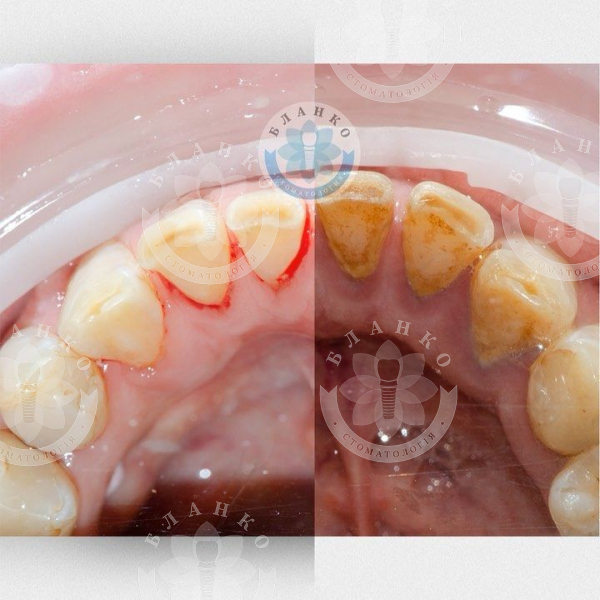

07/10/2020 Чистка зубов перед имплантацией Зачем чистить профессионально зубы перед имплантацией? 🤨 Чтобы на имплант не попали бактерии и он не выпал 🧐